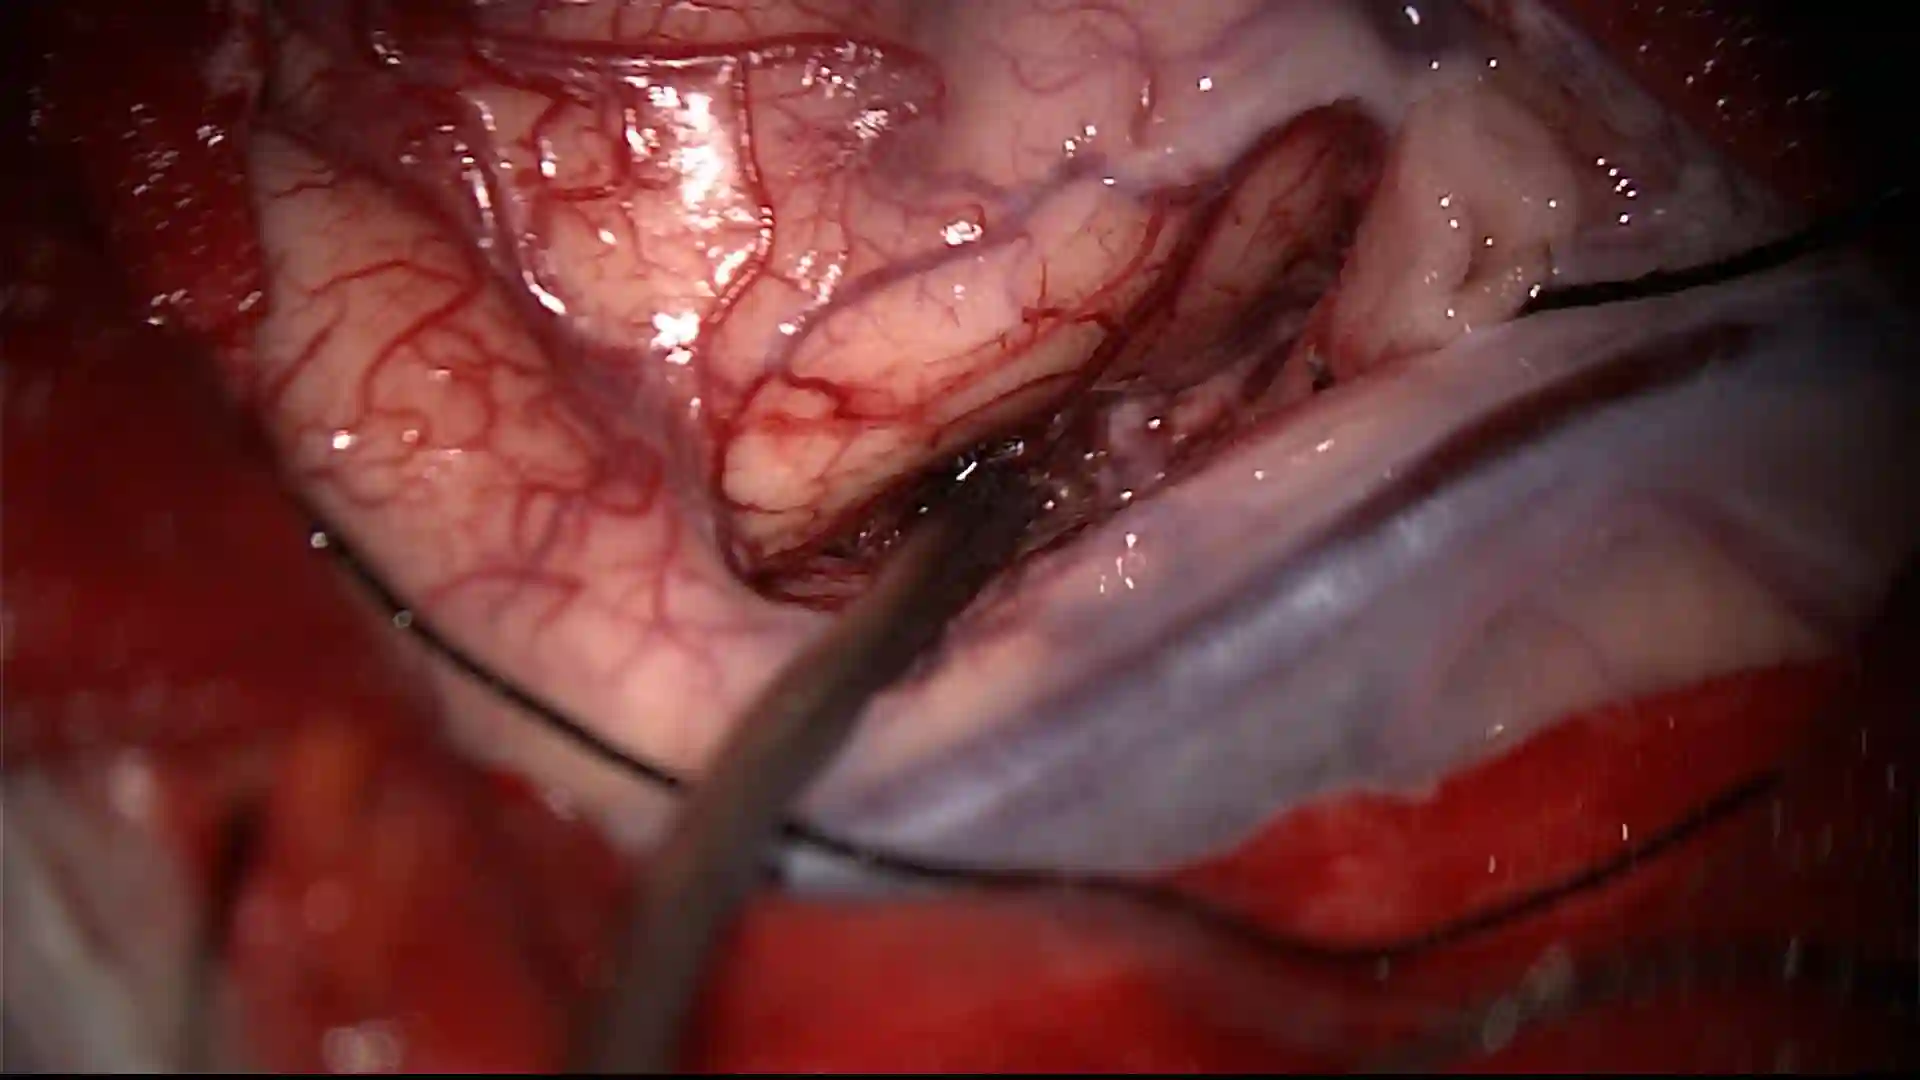

Abbildung

Geöffneter Sulcus während eines chirurgischen Eingriffs. Verwendung einer Mikrowatte zum Aufspreizen des Sulcus.